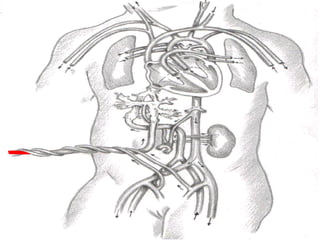

EMBRIOLOGIA

ANATOMIA DEL CORDONUMBILICAL -LONGITUD - GROSOR (DIAMETRO) - GIROS - NUMERO DE VASOS

ANATOMIA Y FISIOLOGIADEL CORDON UMBILICAL